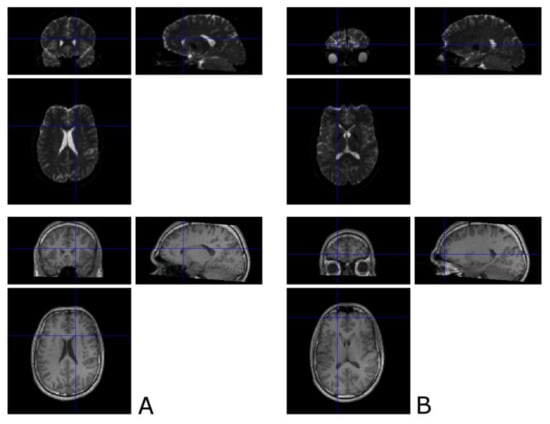

3.2. The Optic Radiation

3.3. The Arcuate Fascicle